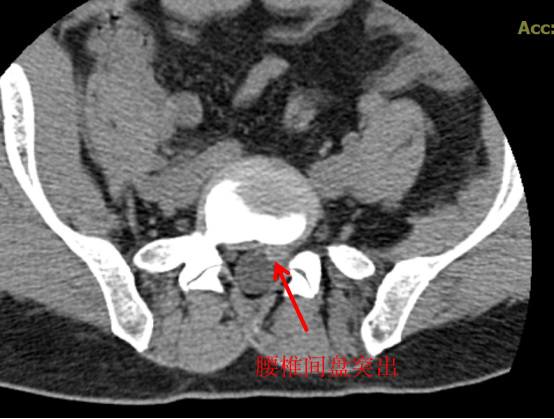

CT 中文名称叫做电子计算机断层扫描,顾名思义就是将需要检查的人体部位,通过电脑切成若干小层,然后把每层的图像显示出来,所以 CT 相对于 X 光片的优点就是细节显示更清楚,一些 X 光片看不出来或看不清的隐匿性骨折,通过 CT 层扫后,就能发现细小的骨折,这样就很大程度上避免了漏诊或误诊。

CT 也可以显示出椎间盘有无突出,椎体内有无骨质破坏、椎管狭窄程度等。所以,如果怀疑一个病人是腰椎间盘突出症,而患者又不愿意做核磁,那就应该首选腰椎 CT。

CT 的优点是可以显示出 X 线检查难以发现的隐匿性骨折,对软组织的显影优于 X 光。缺点是价格稍贵,辐射量更大。